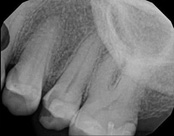

The patient presented with mild pain, a cavity, and a broken filling was evident. After performing diagnostic testing, the diagnosis was: irreversible pulpitis, symptomatic periradicular periodontitis. Root canal therapy was done and the tooth healed well and is still functioning.